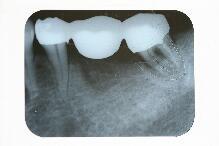

2ヵ月後完成

1ヶ月半は咬合を控えた仮歯にて経過観察しその後最終かぶせ物の形を採りちょうど 2ヶ月経過後セットして終了